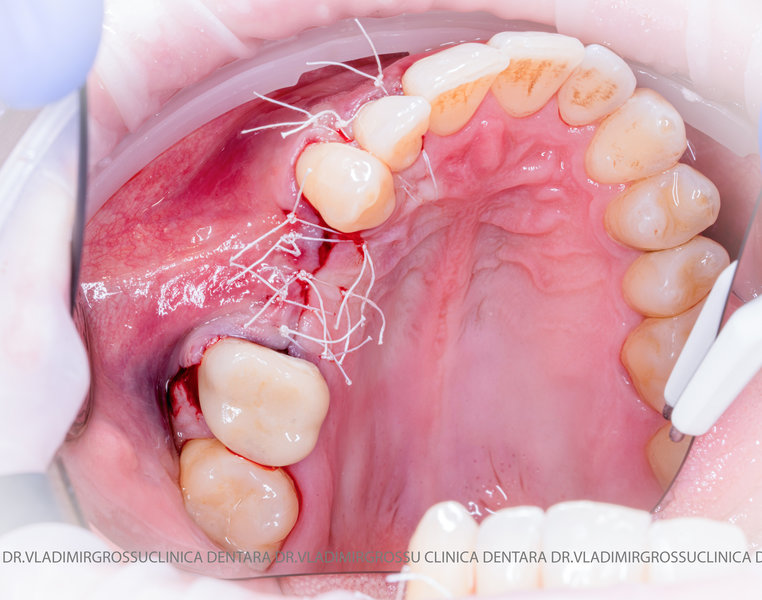

Un element esențial în procedura de aditie osoasă este utilizarea membranelor biologice, care izolează materialul osos de țesuturile moi (gingie) pe durata procesului de vindecare. Cele mai recomandate sunt membranele resorbabile din colagen sau pericard.

Adiția de gingie (gingivoplastia)

Aditia gingivală este o procedură chirurgicală ce corectează diverse probleme estetice și funcționale, cum ar fi recesiunea gingivală. În implantologia modernă, aditia de țesut moale este utilizată aproape în fiecare intervenție de inserție a implantului dentar pentru a asigura un aspect estetic natural și o bună integrare a implantului în cavitatea bucală.